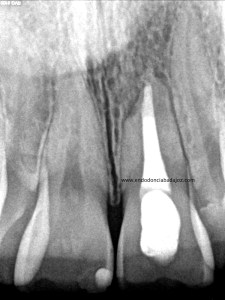

Nos refieren a una chica para retratarle un 2.1, le hicieron un tratamiento de conductos hace unos 5 años y obturaron con pasta. No se recomiendan una obturación con pastas por que no van a conseguir una obturación tridimensional y hermética, y en ocasiones pueden reabsorberse, con lo cual, está contraindicada la obturación solo con pastas.

La paciente presenta un lesión periapical y una tumefacción fluctuante, decidimos retratar.

Colocamos la barrera apical verificando que conseguíamos un buen sellado:

(Rx Mesioradial)                                                 (Rx Ortoradial)